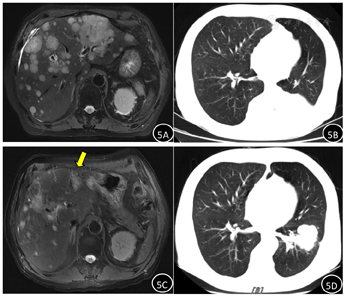

经过2个周期化疗后,患者胸闷、咯血症状较前缓解,2022年10月17日复查上腹部MR增强及胸部CT平扫,肝脏及肺部病灶均明显缩小(图5),尤其原左肝较大肿瘤(黄色箭头所指处)最大径显著缩短,而肺部转移瘤经抗感染及抗肿瘤治疗后,同周围组织牵拉征改善,总体疗效评价部分缓解。